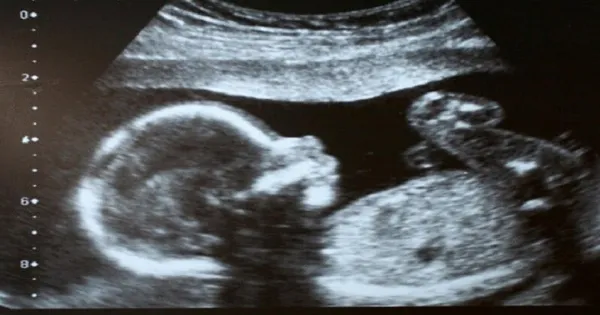

Η Έιμι Πούλ όταν ήταν έγκυος είδε το υπερηχογράφημα των 20 εβδομάδων της, και παρατήρησε ότι κάτι δεν πήγαινε καλά. Όταν είδε τη μύτη του μωρού της…έμεινε άναυδη από τον τρόμο!

Οι γιατροί επιβεβαίωσαν αργότερα, ότι ο γιος της είχε «απροσδόκητα μαλακό ιστό» που μεγάλωνε στο πρόσωπό του.